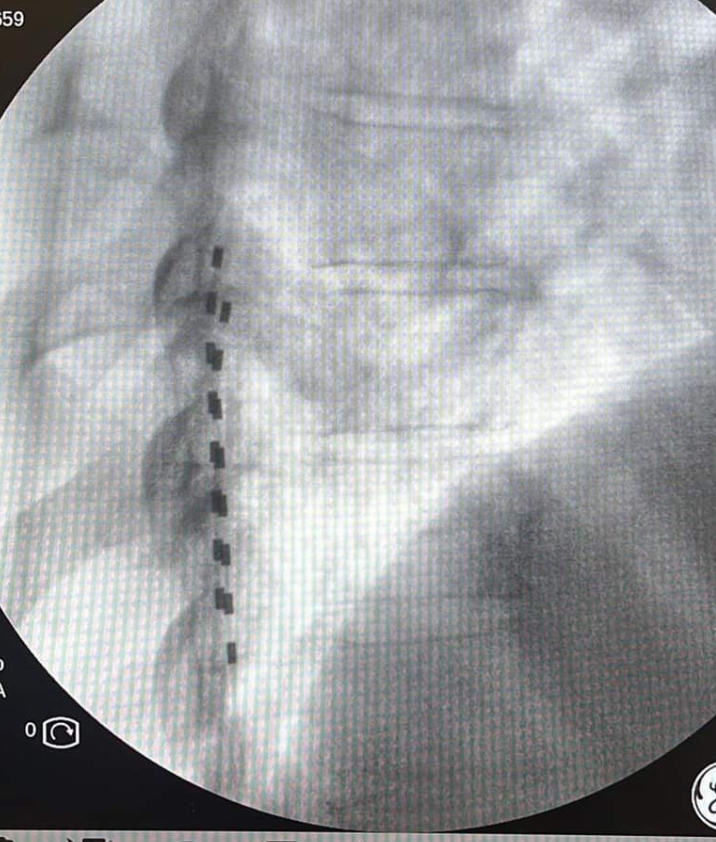

Με τον ασθενή σε πρηνή θέση, υπό τοπική αναισθησία και ακτινοσκοπική καθοδήγηση εμφυτεύονται τα ηλεκτρόδια στον επισκληρίδιο χώρο της σπονδυλικής στήλης και συνδέονται με έναν εξωτερικό διεγέρτη που δίνει τα ερεθίσματα με ένταση που επιλέγεται ανάλογα με τις ανάγκες του ασθενούς. Ο ασθενής για μια περίοδο 7-10 ημερών μπορεί να δοκιμάσει το αποτέλεσμα της διέγερσης και να κρίνει εάν αυτή καλύπτει τις ανάγκες του. Εάν η θεραπεία δεν είναι αποτελεσματική, τα ηλεκτρόδια αφαιρούνται με πολύ εύκολο τρόπο. Επί θετικής απόκρισης, έπεται η διαδικασία τελικής εμφύτευσης του συστήματος.